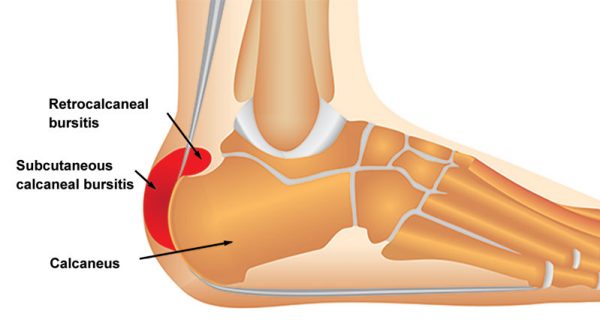

Achilles Bursitis Retrocalcaneal Bursitis Symptoms Causes Treatment